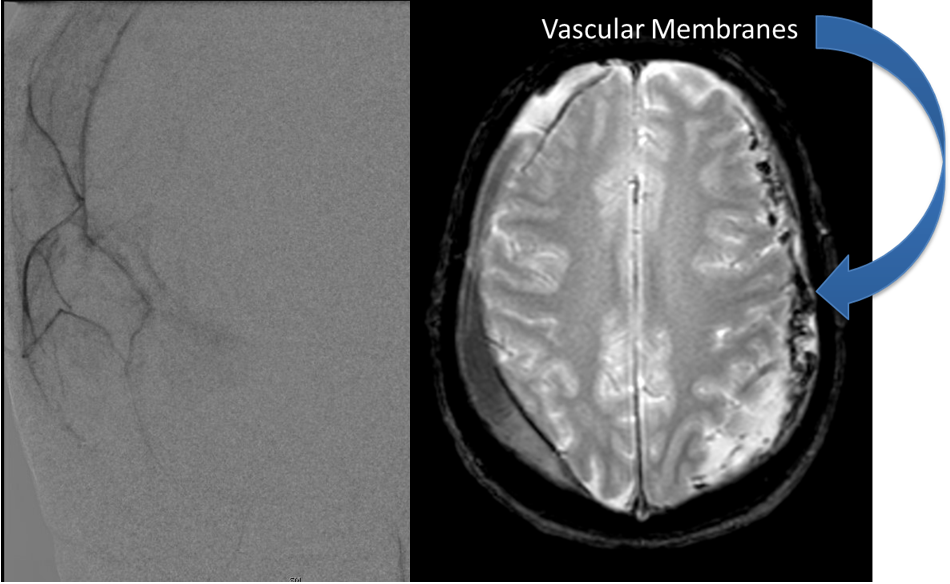

Fig. 4 – Image of the common carotid mobilized external and internal carotid arteries.

Fig. 5 – Image of the vessel after removal of the plaque.

Fig. 6 – Doppler confirms patency of all vessels after closure.

After a discussion with the patient about the risks and possible benefits of revascularization, specifically carotid endarterectomy, the patient agreed, and we proceeded to perform a right carotid endarterectomy with neurophysiologic monitoring. The common carotid external and internal carotid were all identified and then dissected out cleanly and vascular loops placed around them. The common carotid artery was then incised into plaque and the arteriotomy was carried into the internal carotid artery beyond the plaque, and then the plaque shelled out as seen in Figure 4. Once the entire plaque is removed (Figure 5), the inside of the vessel is cleaned out of all remaining debris, prior to closure.

Once the artery is completely closed, and all the clamps are removed, the Doppler confirms good flow, as seen in Figure 6.